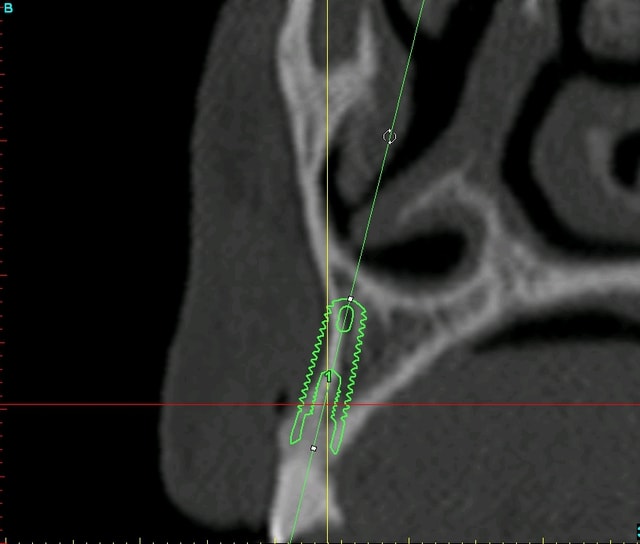

bon, pour que vous puissiez estimer l'ampleur du travail, je vous poste les coupes scan et les photos de la réplique plastique...;-)

quand on voit mes doigts sur les photos, on se rend mieux compte de la minuscule bouche de cette patiente (et je n'ai pas des mains de charretier!!!)

12 xfdtph - Eugenol

13 xpkert - Eugenol

23 wflnz5 - Eugenol